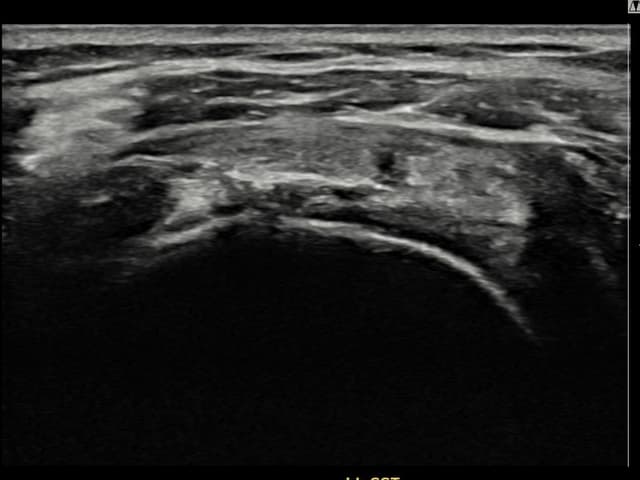

[촬영시기:22.09.19~22.12.09]

[어깨인대 축소봉합술] 우측 어깨 통증이 수개월간 지속되어 내원하셨습니다.